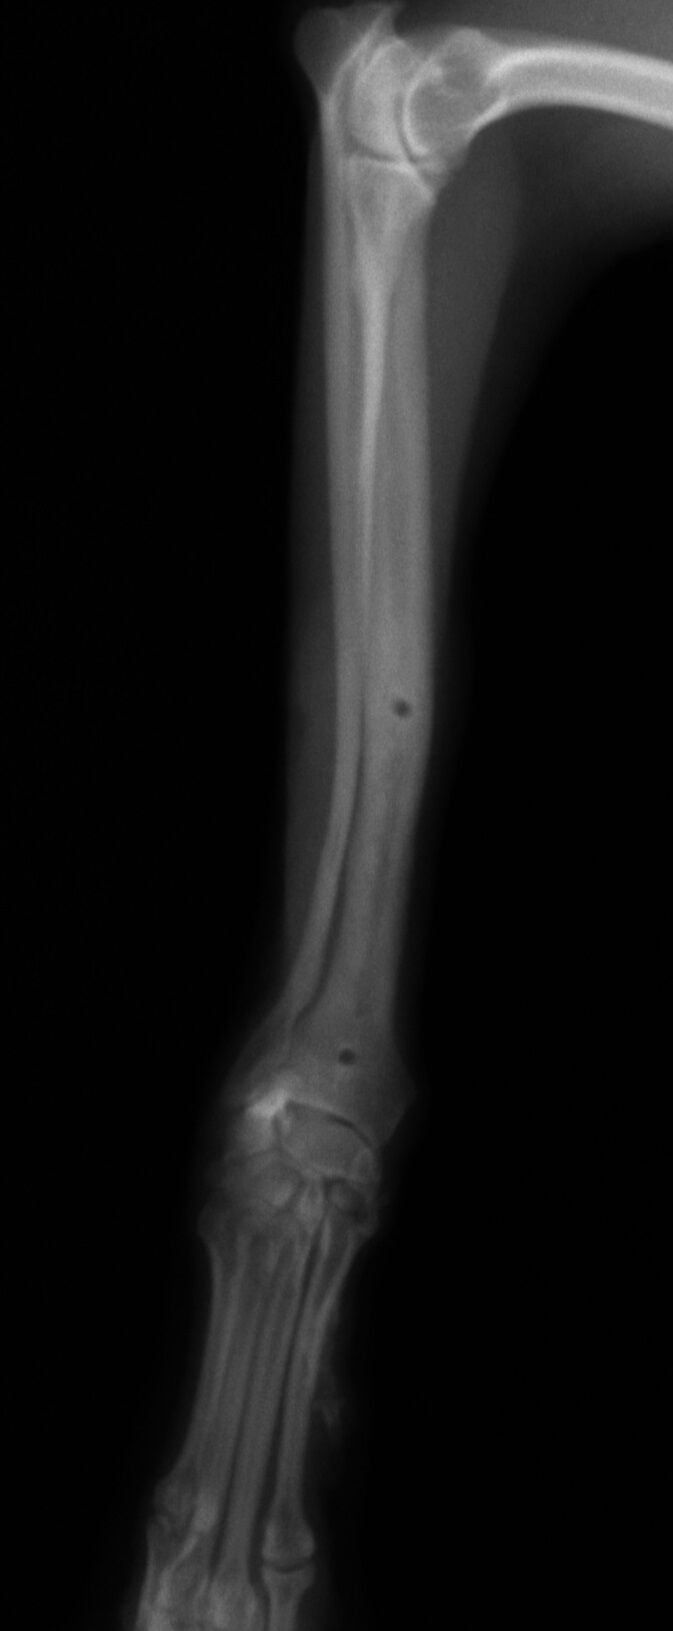

その後、1か月普通に生活していました。レントゲンを撮ったところ、骨は十分に増生していたので、心配ないと判断しプレートを取りました。

プレート除去前

プレート除去後

プレート除去後は何の問題もなく生活しています。うまくいきました。